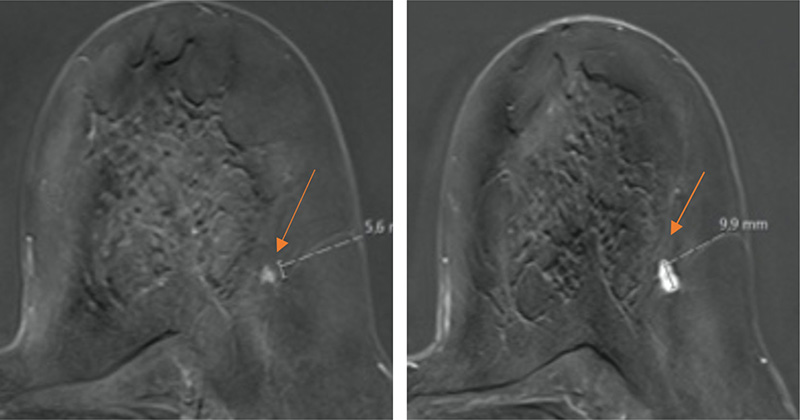

MRT-Mammographien zweier Patientinnen im Rahmen der Vorsorge (ausschnittsweise dargestellt ist nur die linke Mamma). Die Röntgen-Mammographie zeigte bei beiden dichtes Brustgewebe mit hierdurch deutlich eingeschränkter Erkennbarkeit kleiner Tumorherde. Das Karzinom im linken Bild ist 6 mm groß (Pfeil), das im rechten Bild 10 mm (Pfeil). Bei beiden Patientinnen hat mammographisch keine Chance bestanden diese Karzinome zu erkennen. Beide Patientinnen wurden erfolgreich behandelt und geheilt.